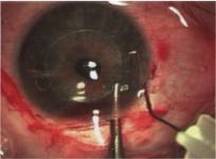

Retinal Detachment |

Retinal Detachment (R.D.) is a separation of the sensory retina from the retinal pigment epithelium(R.P.E) by sub retinal fluid(S.R.F) There are two main types.